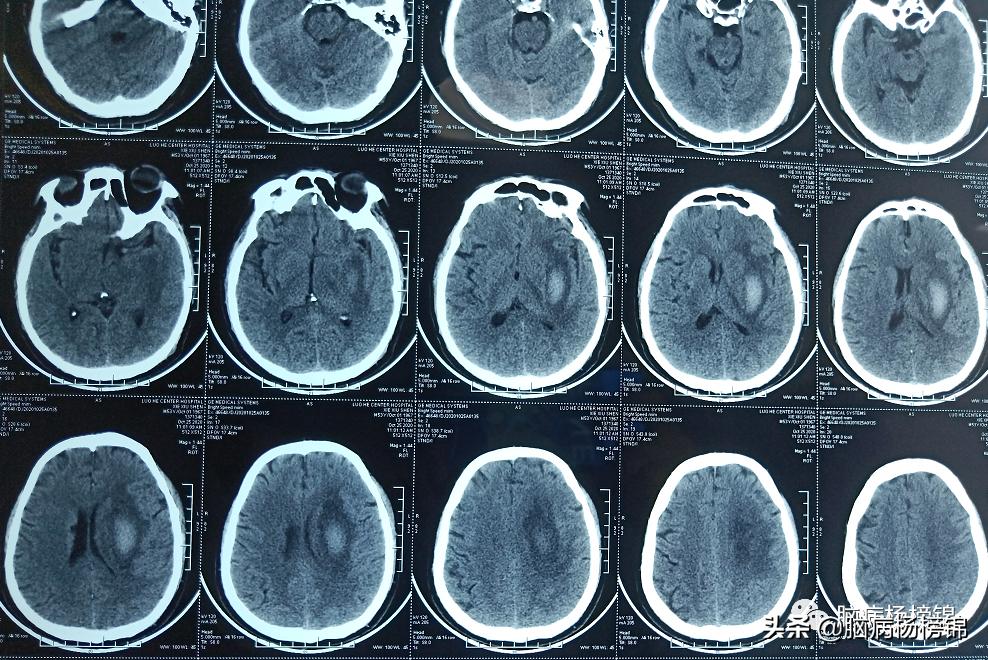

保守治疗25天,血肿大部分吸收。转入漯河六院康复医学科。

发病两个月的片子,遗留软化灶。